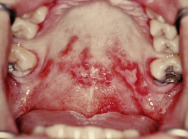

Stomatitis is inflammation involving the oral mucous membranes. Aphthous stomatitis is a chronic, painful, relapsing ulcerative condition of the nonkeratinized mucosa ( Fig. 3.29 )

FIG. 3.29

Aphthous ulcers are most commonly found on the mucous membranes of the oropharynx and appear as shallow, punched-out erosions.

Ulcers of the major form are more common in children and adolescents, usually larger than 1 cm, last many weeks, and heal with scarring ( Fig. 3.30 ).

FIG. 3.30

Large aphthous ulcer (Sutton’s ulcer) on the tongue of a child.

(William Weston Collection)